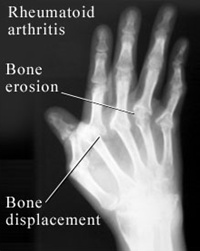

หากผู้ป่วยขาดการรักษาปล่อยทิ้งไว้หลายปี ส่งผลให้โรคดำเนินต่อไปถึงขั้นอันตรายร้ายแรง เพราะเยื่อบุน้ำในข้อจะหนามากขึ้น เส้นเอ็นและเยื่อหุ้มข้อถูกทำลายทำให้ข้อหลวมและหลุดได้ ส่วนที่ถูกทำลายไปจะถูกแทนที่ด้วยเนื้อเยื่อเหนียวเกิดเป็นข้อแข็ง รูปร่างบิดเบี้ยว สร้างความเจ็บปวดทรมาน

การรักษา ผู้ป่วยควรไปพบอายุรแพทย์หรือแพทย์อายุรกรรม ไม่ใช่หมอกระดูกหรือแพทย์ออร์โธปิดิกส์ตั้งแต่ระยะแรกของโรค ทานยาตามแพทย์สั่งเพื่อไม่ให้อาการกำเริบ การวินิจฉัยได้นอกจากอาการเจ็บป่วยแล้วควรตรวจเลือดหารูมาตอยด์ แฟกเตอร์ (Rheumatoid factor) หากมีข้อผิดรูป เมื่อฉายเอกซเรย์จะพบลักษณะการทำลายของข้อ